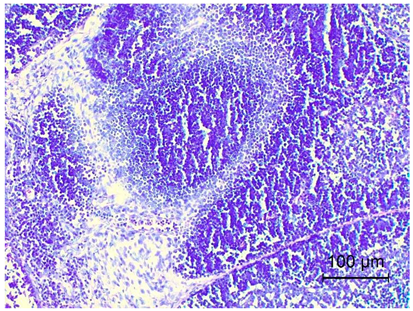

Table 4. Histopathology results of Pekin ducks with short beak and dwarfism syndrome (SBDS).

OrgansSBDS GroupNo. of Figs

IleumSevere inflammatory, covering not only the mucosa but also some of the deeper layers of the intestines and muscle membrane and stimulating lymphoid follicles.

Disruption of small intestinal villi, and the disappearance of normal tissue structure.

Applsci 14 08637 i006